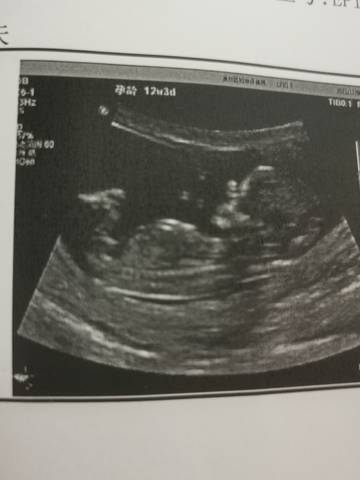

为什么这个nt看起来和b超差不多,看完只觉得宝宝头有点大,也没有写心率什么的

亲爱的,你好,nt检查呢 主要是检查胎儿颈部透明度的,还是不太一样的。 b超检查可能会简单一些